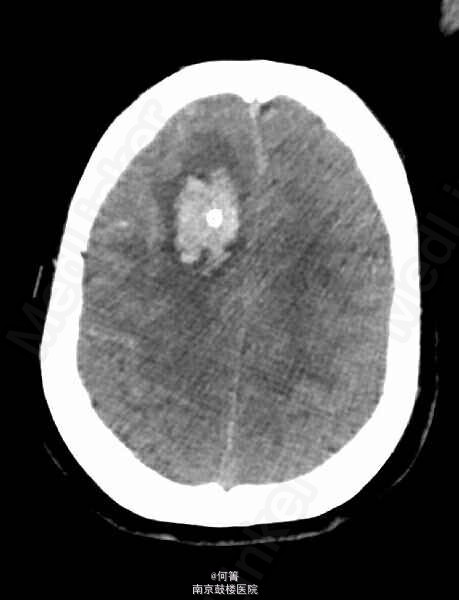

查体:BP:158/103mmHg,余生命体征平稳。专科查体:嗜睡状,呼之能应,查体欠合作;右侧额部留置有脑室外引流管,引出淡红色脑脊液;颈项强直。 辅助检查:CTA:蛛网膜下腔出血,脑室积血,右侧额叶血肿伴灶周水肿,脑实质明显肿胀,中线局部左移,右侧脑室见引流管。基底动脉瘤,其内密度不均匀,可疑血栓形成,大小约1.0x1.5cm;左侧椎动脉颅内段动脉瘤,大小约0.6x0.5cm;左侧大脑中动脉M1及M2D段交界区动脉瘤,截面大小约0.6*0.6厘米;右侧颈内动脉终段、左侧大脑中动脉M1段及椎动脉管腔不均匀,局部增粗,管壁欠光整。

诊断:1、蛛网膜下腔出血,2、颅内多发动脉瘤,3、高血压病 3级 极高危。治疗:予以抗血管痉挛、抑酸护胃、纠正低钾及对症治疗,行DSA检查,示基底动脉梭形动脉瘤;左侧小脑后下动脉起始部动脉瘤;左侧大脑中动脉分叉部膨大。行介入下动脉瘤夹闭术。